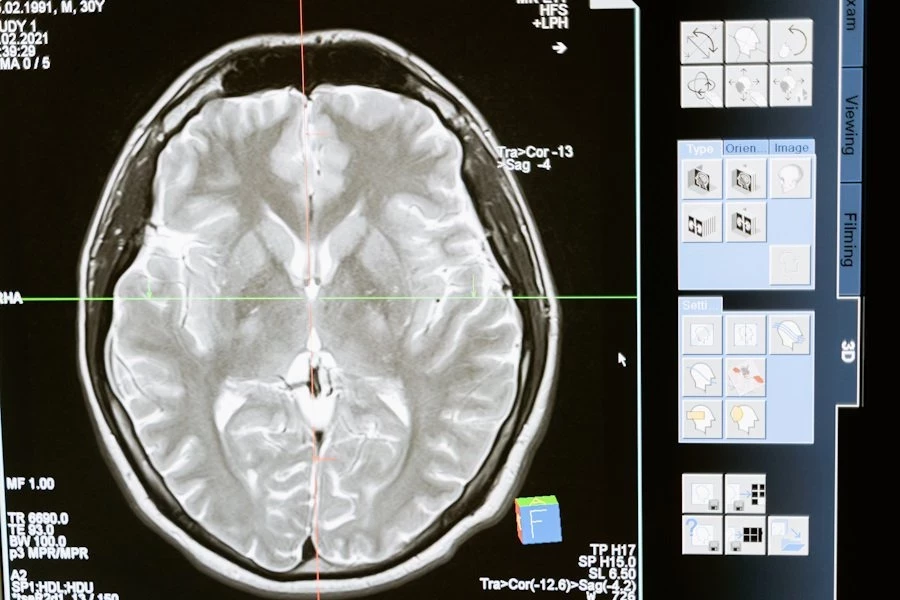

Фото из открытых источников

Ученые из Universitat Pompeu Fabra (Испания) сделали удивительное открытие: объем зрительной рабочей памяти человека можно увеличить с помощью звуковой и визуальной стимуляции. Это открытие открывает новые перспективы в улучшении когнитивных способностей и, возможно, лечении ряда заболеваний, сообщает Communications Psychology.

Зрительная рабочая память — это система мозга, которая помогает нам временно удерживать важные визуальные детали, например, при чтении, решении головоломок или сравнении объектов. Исследователи опирались на тета-гамма-модель, которая связывает объем рабочей памяти с частотой тета-колебаний мозга. Эти ритмичные волны появляются в переходе от бодрствования к расслаблению.